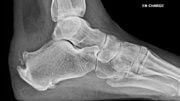

Deux mécanismes principaux sont décrits :

- le conflit de Haglund : une proéminence osseuse du calcanéum frotte contre le tendon et crée une inflammation,

- la forme dégénérative : le tendon s’use progressivement, parfois avec des dépôts calcifiés (enthésophytes). Souvent, ces deux mécanismes se combinent.

Imagerie